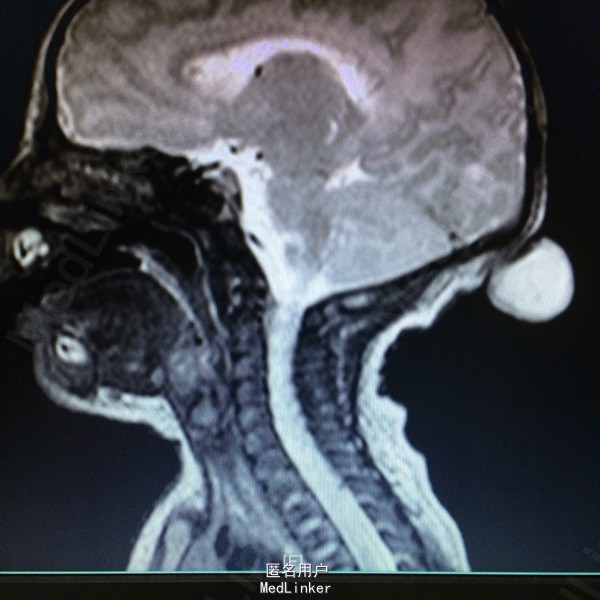

主诉:发现枕部包块1月余 病史:患儿2月大,第3胎第3产,经剖宫产,查体发现枕后部有一圆形肿物突出,约等3*3大小,透光实验阳性,质软。

查体:神志清醒,枕后部可见一圆形肿物突出,约3*3cm大小。质软,表面无溃疡等 辅助检查:胸片提示新生儿羊水吸入综合症,头颅MR提示局部脑脊膜膨出

诊断:后枕部脑脊膜膨出 处理:行脑脊膜膨出修补术,病理提示符合脑脊膜膨出